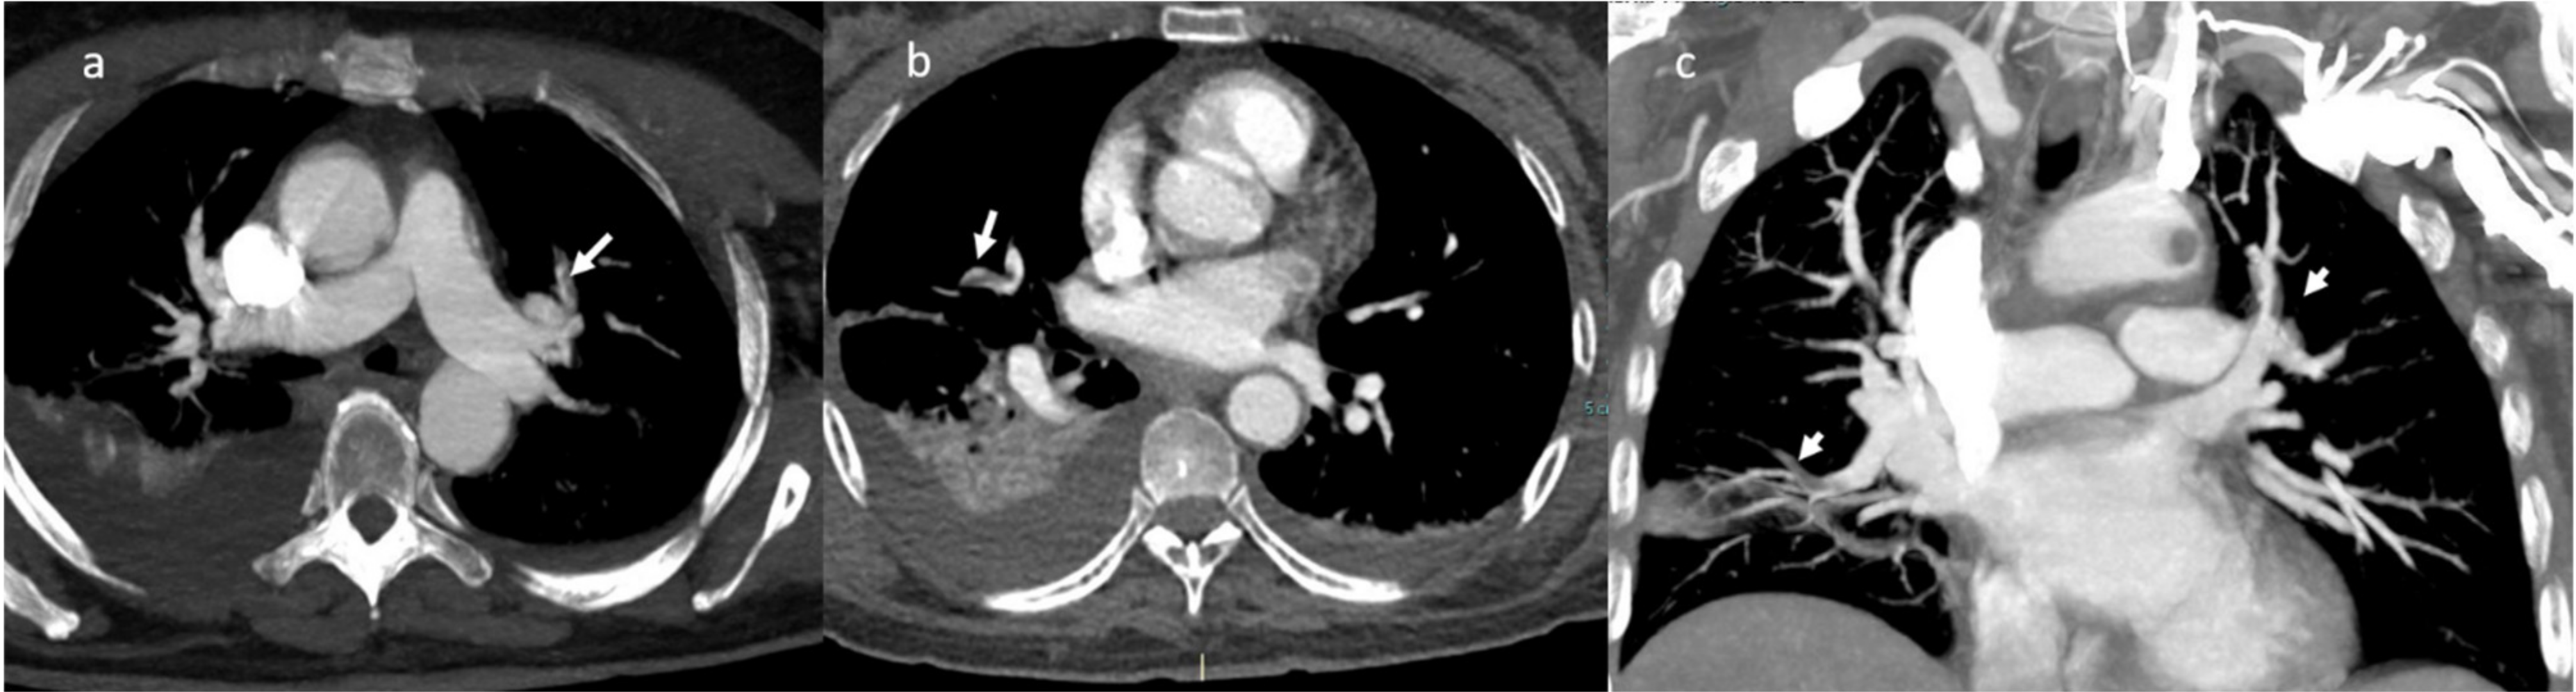

2. Case